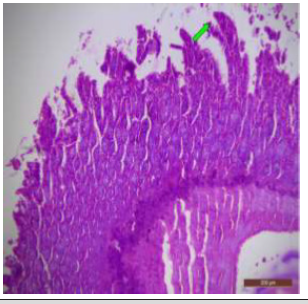

Scanning electron microscopic examination of the ileum from the control rat revealed typical leaf like villi with smooth microvillous surface (Figure 41). A prominent tongue shaped villous tip with a broad base and blunt apex was also observed in the ileum of control rat (Figure 42). In fluoridated rats, fused villi which give doughnut like appearance and Paneth cells were also present (Figure 43). The ileal mucosa of fluorotic rats revealed erosions. At the villous surface, stratified cells and some exfoliated cell sheets were also seen in several regions (Figure 44). The fluorotic ileal mucosa had fissures at the base of villi were present. The tips were curved and broken and showed signs of erosions (Figure 45). SEM examination of ileum from fluoridated rats showed corrugated appearance and the villi abruptly became stubbier, slightly curved and swollen (Figure 46).

Figure 41: Scanning electron micrograph of ileum of control rat showing leaf like villi with smooth microvillous surface. X 607.